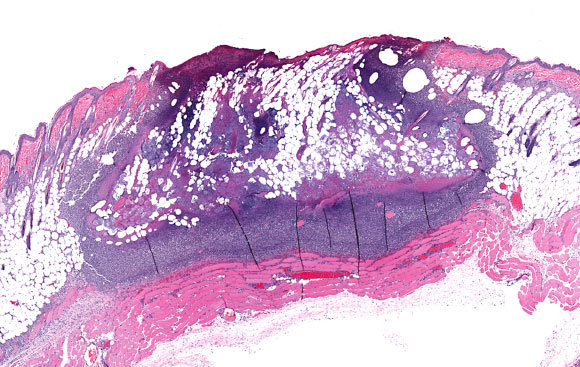

إنه، لحسن الحظ، مرض نادر جدًّا مع كونه خطير. صورة بالمجهر لِتلوّث الجلد ببكتيريا ستافيلوكوكوس | تصوير: vetpathologist, Shutterstock